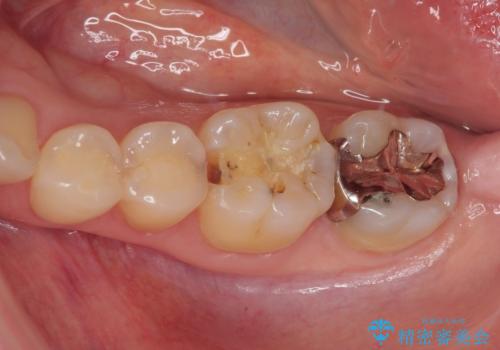

- 銀歯がとれたのでやり替えたいとのことで来院された患者様です。来院時特に症状もなく金属の詰め物(メタルインレー)がとれたのでセラミックの詰め物(セラミックインレー)にやり替えていくことになりました。また患者様のご希望によりひとつ後ろの歯の金属の詰め物(メタルインレー)のやり替えも同時に治療していくことになりました。